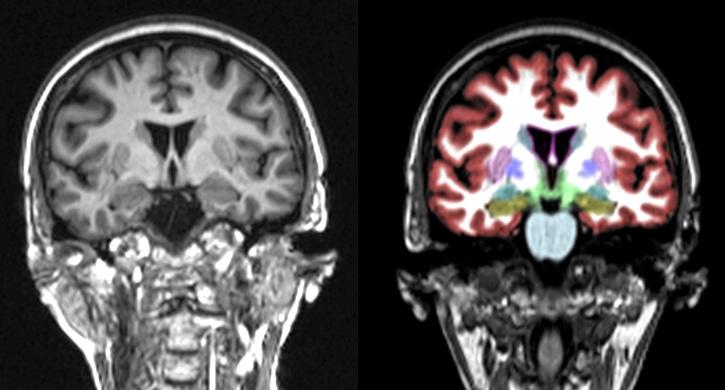

• MRI scans of the brain can be combined with a program called NeuroQuant® that will give a volumetric measurement of all the brain structures.

• NeuroQuant® allows a comparison of the size of each brain structure to those of age-matched controls. This lets us see if the brain structures are atrophied (neurodegeneration) or enlarged (from inflammation).

• We had a completely unexpected and unprecedented finding: Even the MRI head scans showed statistically significant improvements!

She recently completed a collaboration with Dr. Dale Bredesen on a prospective clinical trial to reverse mild cognitive impairment and early dementia: Precision Medicine Approach to Alzheimer’s Disease: Successful Pilot Project which was published in the Journal of Alzheimer’s Disease August 2022. In this landmark study, a majority (84%) of the study patients had improvement in their cognitive decline, including their MRI head scans.